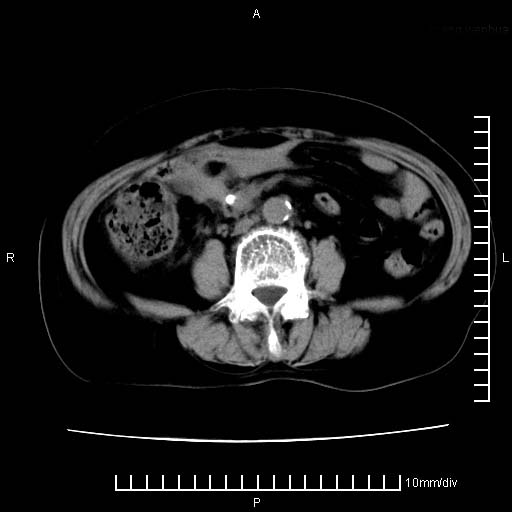

下腹疼痛2月,加重并呕吐2天,下腹压痛,反跳痛。白细胞1万2.

下腹至盆腔较大包块,与邻近肠管关系密切,下腹疼痛2月,加重并呕吐2天,下腹压痛,反跳痛。白细胞1万2.

由于没有做肠道准备很难分清是哪根肠管,但看位置考虑为升结肠回盲部的问题,我首先考虑化脓性阑尾炎,不除外结肠癌合并感染化脓。建议做增强进一步明确。

补充:道格拉斯腔内有积液,且密度较高,显然提示有感染。

考虑右侧卵巢囊肿伴感染可能性大。

附件实性肿块有坏死 考虑卵巢癌

来源于附件占位—多考虑:卵巢癌!

不知道大家可要注意下腹腔小肠旁不规则结节状灶,部分钙化,是否要考虑小肠腺癌.盆腔包块可能考虑脓肿.